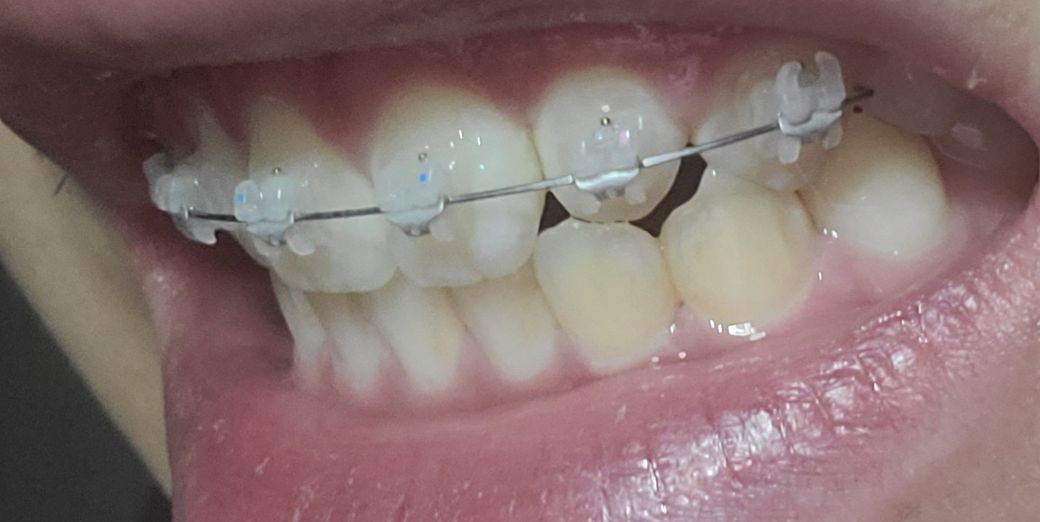

교정전부터 뼈 비대칭 때문에 치아중심선이 조금 안맞은 상태였는데 두번째앞니 전방으로 빼고있는 상태인데 두번째 앞니를 앞으로 빼다보면 교정완료후에 치아중심선이 더 안맞아보이거나 틀어질수도 있나요?

• 2번 째 사진